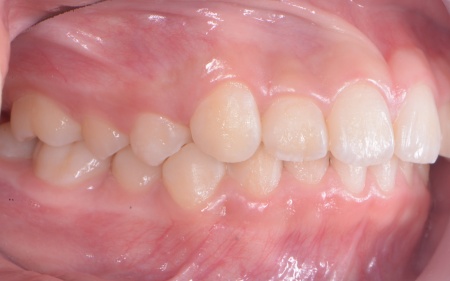

10歳女の子 成長期を利用した小児矯正治療で八重歯を改善した症例

「上前歯が八重歯になってきたのが気になる」とご相談いただきました。

拝見したところ、上の犬歯が歯列の外側に飛び出すように生えている、いわゆる八重歯でした。

さらに、上下の歯全体がデコボコに生えている「叢生(そうせい)」と呼ばれる状態で、これは歯が正しい位置に並ぶためのスペースが不足していることが原因だと考えられます。